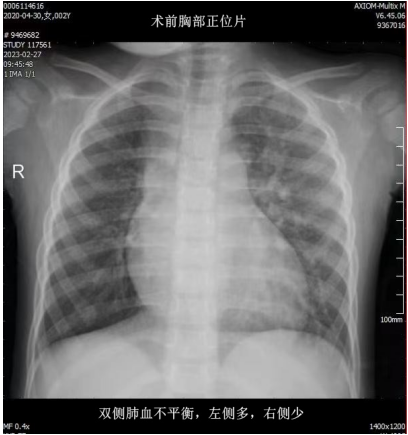

近日,兰大二院心脏外科为一名2岁双侧肺血不平衡先天性心脏病患儿成功实施了右侧肺动脉重建手术,同期矫治了房间隔缺损、动脉导管未闭及粗大的体-肺动脉侧支,患儿术后恢复良好,复杂先心畸形得到矫治,现已治愈出院。

患儿出生后即有口唇紫绀、易“感冒”等症状,并多次发生不易治愈的肺炎,曾辗转省内外多家医院就医,均未能得到有效治疗。遂来兰大二院就诊,心脏外科高秉仁教授对患儿病情进行仔细评估后,收住入院。完善相关检查,经全科讨论后,确诊为一种罕见、复杂的先天性心脏畸形疾病,并拟行手术治疗。

该手术优势在于采用自体血管组织重建右肺动脉后壁,使重建的右肺动脉具备一定的生长能力,最大限度地避免未来进行二次手术。同时,手术治疗后患儿原有严重的双侧肺血及肺动脉压力不平衡状态得到了有效矫治,患儿肺血及肺动脉压力回归正常。